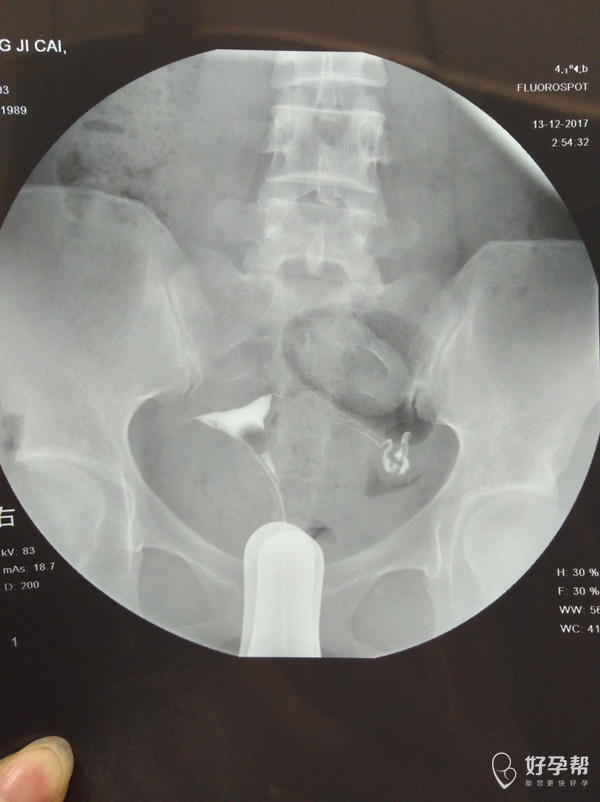

输卵管通而不畅应该怎么治疗

麻烦医生指点,输卵管通而不畅要怎么治疗?我的右侧输卵管部分切除,所有希望都寄托在这跟管上了,我不想试管,想自然怀孕,帮帮忙指点

,谢谢!从哪里看的出通而不畅的,也帮忙指点一下